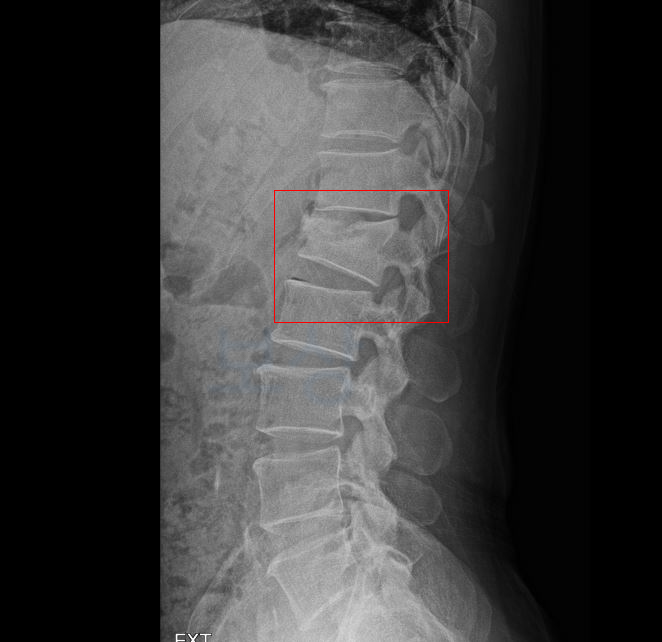

이 사고로 이@@님은 **L1 부위의 골절 S3202 **진단을 받아 최소 12주간의 침상안정이 필요했는데요 L1 부의의 골절은 lumbar 의 약어로 요추 1번 부위의 골절을 의미합니다.

부산 손해사정사 lumbar 즉 L1 부위의 골절 보험 처리